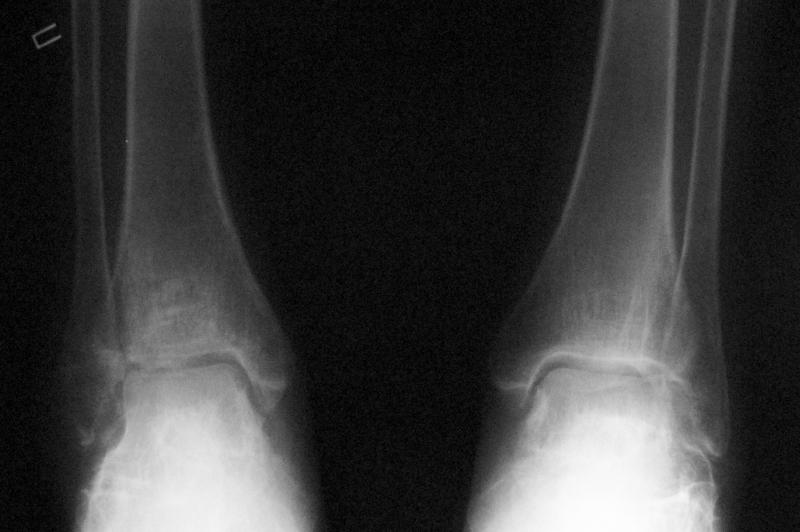

Уважаемые коллеги! Помогите определится с тактикой лечения.Оскольчатый импрессионный перелом заднего края правой большеберцовой (Пилон?) кости 5-ти недельной давности на фоне неправильно сросшихся переломов пяточных костей (травма в 1991г.), ДОА подтаранных суставов 3 ст. До последней травмы больная ходила без особых проблем и работала пекарем (работа на ногах).Суть проблемы в том, что открытая анатомическая репозиция в таком сроке представляется мне крайне травматичной, что может привести к неблагоприятному функциональному исходу.Варианты решения:1) оставить "как есть" с последующим артродезом после развития ДОА2) выполнить остеотомию и попытаться низвести основную часть суставной поверхности3) выполнить попытку анатомической репозиции из задне-латерального??? доступа.

По снимкам довольно сохранный сустав, и такой сустав желательно попытаться восстановить всеми возможными мерами.